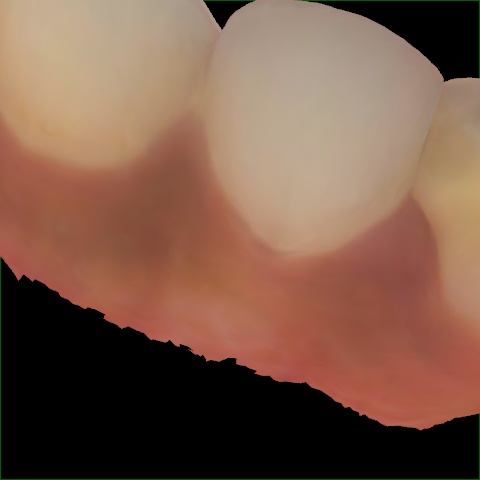

Annotated as "Bad"